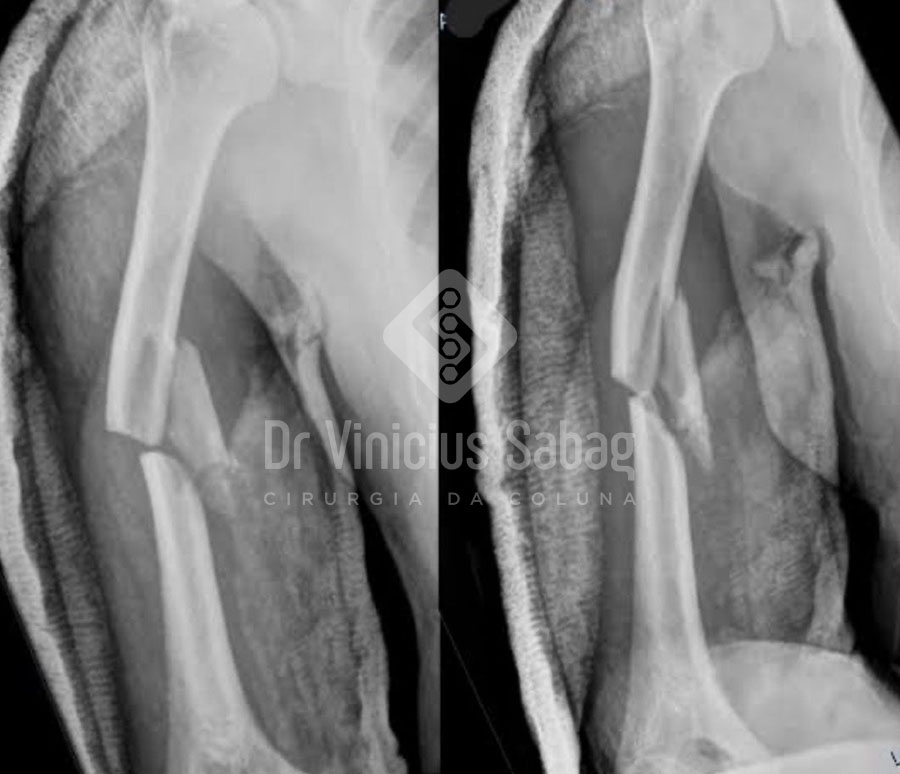

A fratura ocorre quando há quebra parcial ou total de um osso. Ela pode ser causada por traumas diretos, quedas, acidentes ou até por fragilidade óssea, como nos casos de osteoporose.

Em alguns casos, pode haver fratura exposta, quando o osso atravessa a pele, exigindo atendimento médico imediato.

Diagnóstico

O diagnóstico geralmente é confirmado pela radiografia. Em casos mais complexos, podem ser necessários exames complementares para avaliar a lesão nos tecidos adjacentes.

O tratamento depende do tipo de fratura e pode incluir:

- Imobilização com gesso ou órtese

- Uso de talas

- Cirurgia para fixação do osso com placas, parafusos ou hastes